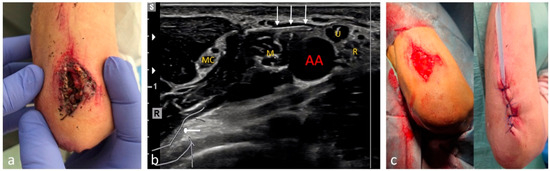

| Foreign body removal | 14 | Depending on location |

| Hematomas and hemarthroses | 15 | Depending on location |

| Soft-tissue infections (extremities) | 46 | Depending on location |

| Large lacerations/cuts | 12 | Depending on location |